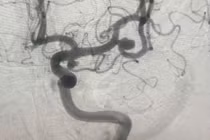

| Hình ảnh vị trí túi phình. (Ảnh: BVCC) |